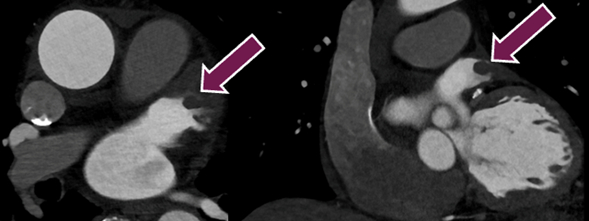

We hypothesized that non-ECG-gated high-pitch dual-source PCCT angiography from the diaphragm to the brain might provide added clinical value in detecting cardiac stroke sources during initial stroke imaging while maintaining optimal brain and neck image quality.

Consecutive patients with a clinical suspicion of acute stroke imaged with a PCCT system between October 4th, 2023 and April 13th, 2024 at a Swedish comprehensive stroke center were included. Diaphragm to brain coverage was obtained in an acquisition time of 1.3 seconds; on average, yielding a dose-length product of 360 mGy*cm for the study participants (2.34 mSv). Image quality was graded using a 4-point Likert scale. Images were assessed for cardiac stroke sources. Where available, reference standard echocardiography results were collected.

Image quality of the heart was excellent in 19 scans (9.8%) good in 97 (50.3%), moderate in 72 (37.3%), and poor in 5 scans (2.6%). Fourteen (7.3%) certain or probable interatrial septal defects were found in the study population. In the imaging-confirmed ischemic stroke subgroup, six certain or probable cardiac thrombi were found (4.8%). Additionally, a possible cardiac thrombus was found in 31 instances (24.6%). Three aortic valve vegetations were found (2.4%), all confirmed by echocardiography.

Non-ECG-gated high-pitch dual-source PCCT angiography typically provides images of high quality, at virtually no time expense while maintaining a reasonably low radiation exposure. Non-gated PCCT angiography is a promising technique to be used as a primary screening method for cardioembolic stroke.